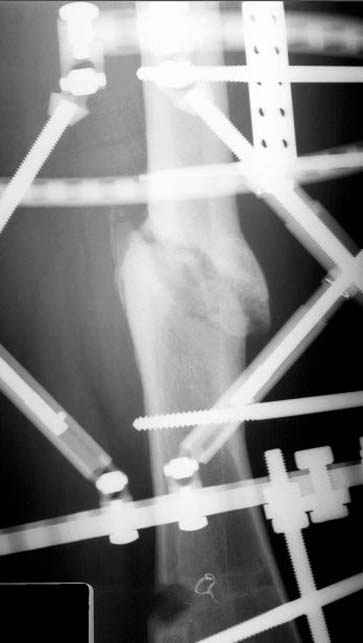

Отправитель: Djoldas Kuldjanov 23 Ноябрь 2004, 18:21

пластическая модель; и коррекция бедра аппаратом Илизарова.

Имею другие снимки тоже, получится как отчет о моей работе.

• Re: Hip joint

Отправитель: Evgueny Tschekashkin 23 Ноябрь 2004, 21:28

Уважаемый Джолдас,

Почему не замена гвоздя с рассверливанием, а аппарат?

Отправитель: Alexander Chelnokov 23 Ноябрь 2004, 21:29

Попробую угадать - была инфекция?

Отправитель: Evgueny Tschekashkin 24 Ноябрь 2004, 21:09

хотя даже если бы и инфекция , то nail exchange с рассверливанием канала - вариант дебрайдмента) Я думаю, что последовательность развития событий:

Узкий к-м канал - тонкий гвоздь- усталостный перелом дистальных винтов - развитие нестабильности и как ее результат остеолиз вокруг гвоздя - деформация анатомической оси бедра. Похоже, что я понял почему аппарат, а не новый гвоздь:-)

Отправитель: Alexander Chelnokov 24 Ноябрь 2004, 21:11

ET> хотя даже если бы и инфекция , то nail exchange с рассверливанием канала -

ET> вариант дебрайдмента)

Да, но если, скажем, течет из инфицированных каналов запирающих винтов, да инфекция в дистальном метафизе бедра - устанешь сверлить.

Аппарат в таком случае средство из серии "тише едешь - дальше будешь".

ET> Я думаю, что последовательность развития событий:

[...]

ET> деформация анатомической оси бедра.

Да, наверно. Но если ничего другого нету, ту небольшую деформацию можно было устранить дистрактором одномоментно ввести другой гвоздь.

ET> Похоже, что я понял почему аппарат, а не новый гвоздь:-)

Отправитель: Evgueny Tschekashkin 24 Ноябрь 2004, 21:13

> Да, но если, скажем, течет из инфицированных каналов запирающих винтов, да инфекция в дистальном метафизе бедра - устанешь сверлить.

ЕТ-Теоретически это возможно, а практически трудно представить - все-таки уровень медицинского сервиса высок, поэтому вряд ли инфекционное воспаление может зайти так далеко.....

> Тогда делись догадкой скорей!

ЕТ - Изначально костно-мозговой канал бедра был узкий, дальнейшее его рассверливание ещё больше скомпрометирует прочность бедра( латеральный кортекс дистального отломка уже истончен), приведет к дефекту наружной стенки - хотя это только мои догадки - хотелось бы знать мнение Джолдаса о выбранной тактике.